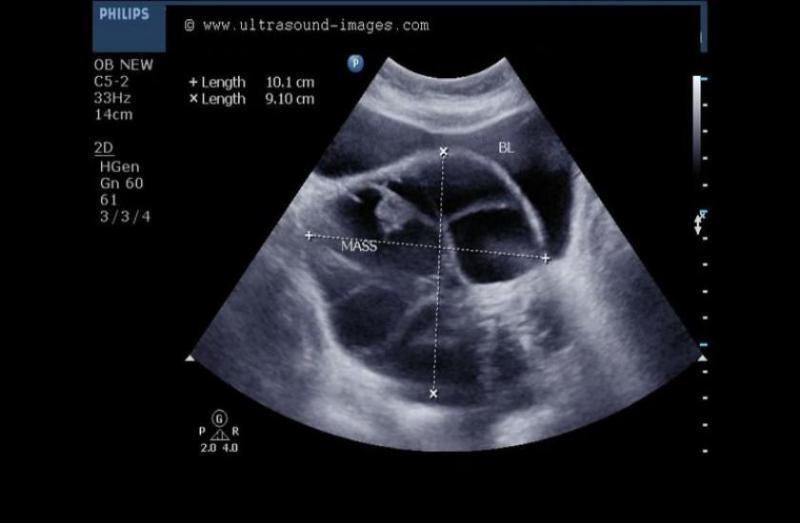

इन सारी बातों से त्रस्त कायला वहां स्थित जैक्सन नामक हॉस्पिटल में पहुंची। वहां डॉक्टर्स ने परीक्षणों के बाद जो बताया उसे सुनकर कायला के होश उड़ गए।डॉक्टरों के मुताबिक, कायला को'म्यूकिनस सिस्टाडेनाेमा' है। यह एक तरह का ट्यूमर होता है, जो ओवरी यानि कि अंडाशय में होता है।

कायला की बिगड़ती हुई स्थिति को देखकर डॉक्टर्स ने उसे तुरंत सर्जरी करवाने की सलाह दी। दर्द और बाकी परेशानियों से त्रस्त कायला हिम्मत जुटाकर इस बात के लिए राजी हो गई। इसके बाद डॉक्टरों ने ऑपरेशन कर कायला के पेट से उस ट्यूमर को निकाला। ट्यूमर के बाहर निकलते ही कायला का वजन झट से 34 किलो कम हो गया।

डॉक्टर्स का कहना था कि अगर समय पर सर्जरी नहीं की जाती तो यह शरीर के दूसरे अंगों को अपने चपेट में ले सकती थी। आॅपरेशन के बाद अभी कायला बिल्कुल ठीक है। कायला अपने उस दौर के अनुभव के बारे में बात करते हुए कहती है कि, वह बहुत ही भयानक अनुभव था। जब उन्होंने खुद ट्यूमर को देखा तो वह डर के मारे सहम गई। उसे काफी हैरानी भी हुई। उस ट्यूमर का आकार एक बड़े से तरबूज की तरह था।